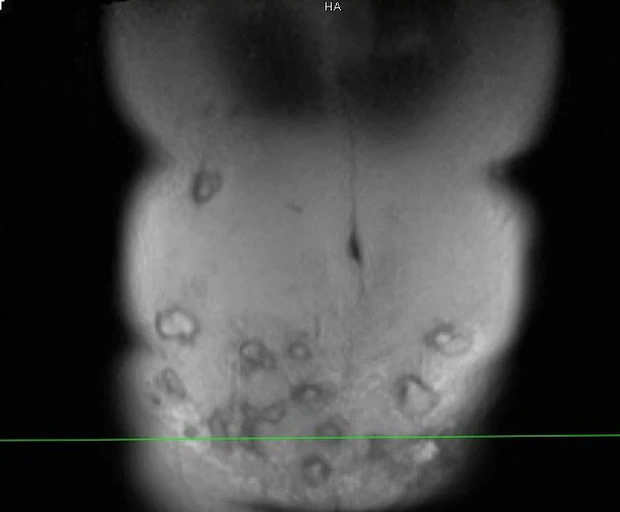

Bệnh nhân tổn thương sau khi đi thẩm mỹ vùng bụng tại spa. Ảnh: BSCC.

Bác sĩ Minh cho biết qua thăm khám, vùng thành bụng bệnh nhân bị viêm phản ứng nặng, vùng da ngoài thành bụng đỏ, nổi gồ ghề, sờ bên dưới có hàng chục khối tổ chức vón cục, áp xe.....

“Bệnh nhân này có thể tạo hình lại thành bụng, đồng thời xử lý được các khối áp xe (khoảng 20 khối lớn nhỏ). Tuy nhiên do vùng tiêm rộng nên việc lấy hết ổ áp xe không dễ dàng. Với những khối áp xe ở vị trí cao như hạ sườn, quá trình xử lý sẽ để lại sẹo, gây mất thẩm mỹ”, bác sĩ Minh chia sẻ.